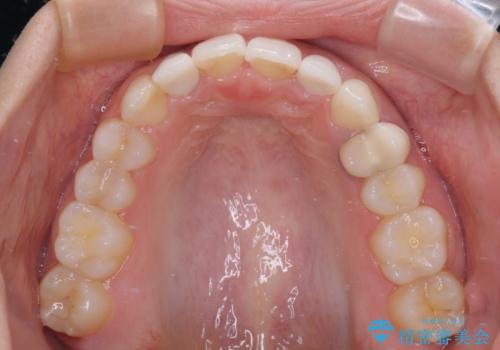

- 前歯の歯並びと神経を取って変色してしまった前歯を気にして来院された患者様です。

上下前歯の歯列不正はインビザラインにより整え、その後に、前歯2本をオールセラミッククラウンにて補綴治療することとしました。

下顎前歯が1本欠損しており、下顎歯列の大きさが本来よりも小さいため、上顎歯列とのバランスが悪く、深い咬み合わせになっていました。

上顎にIPRを多用して歯列の大きさを小さくするよう試みましたが、理想的な咬み合わせまでには改善させることはできませんでした。